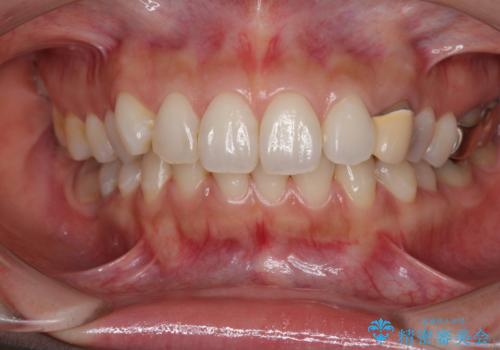

保険診療では樹脂を用いた素材で製作するため、水分が吸収されやすく、一緒に色素が取り込まれるために変色をしてしまいます。

また、裏打ちに主に銀を用いた金属材料を使用するため、金属自体が黒くなったり、イオンとなり溶け出したりして、歯肉ラインが黒くなってしまうことがあります。

前歯1本の治療では、オールセラミッククラウンといえども周囲と調和しなければ自然な仕上がりにはなりません。

今回は既製の色調のセラミックを選択されましたが、もっと色合いにこだわりたい場合には、オーダーメイドタイプのセラミッククラウンをご選択いただいています。